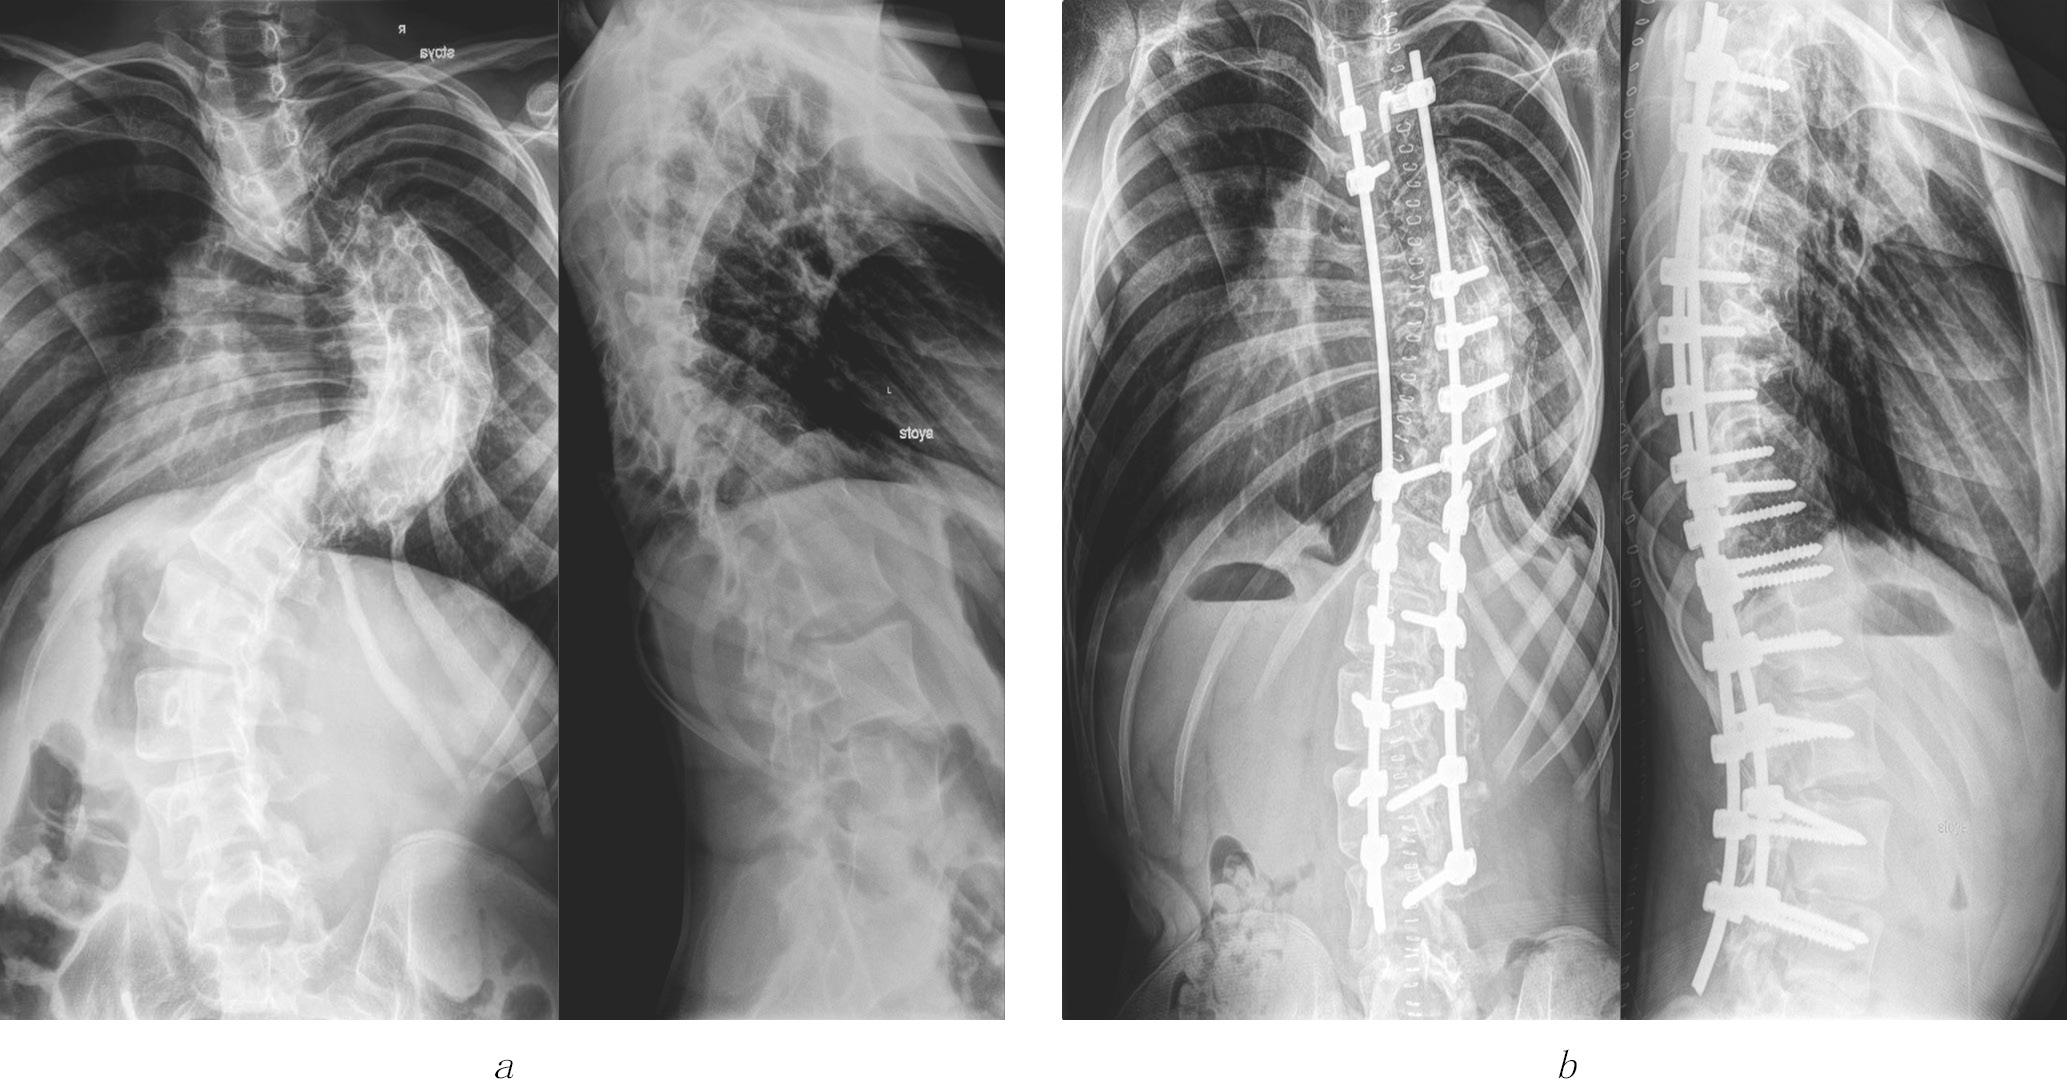

图1显示了患者S手术时的X线影像,

当时17岁,术后两年间出现特发性右侧胸椎侧弯。

图1.17岁患者S的放射片:(a)术前;(b)椎间盘切除术后,行融合术、颅骨胫骨牵引,并通过多支

撑性外科器械系统联合椎体Th7楔形切除术进行畸形矫正